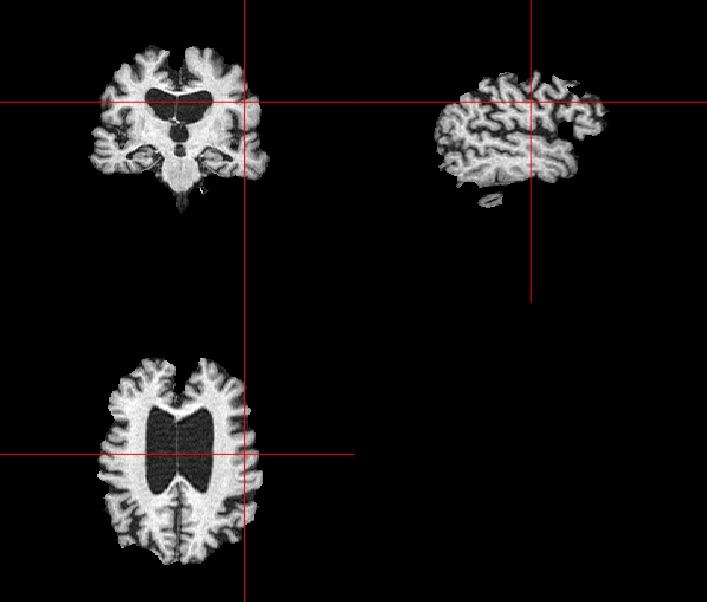

German physicist Alois Alzheimer laid the foundations of most of the modern understanding of the underlying causes of this disorder when he noticed the common biomarkers through histological techniques on the brains of his diseased patients [5]. Recent technologies exist, such as MRI, which helps in visualising atrophy or change in tissue volume of such biomarkers over a period of time, or fMRI, which can identify high-resolution activation of different brain regions during various cognitive tasks [6]. Fig. 1 shows the example of an AD patient’s raw unprocessed brain slice in different planes obtained from MR imaging in a magnetization-prepared rapid gradient-echo (MP-RAGE) sequence.

Refer to caption

(a)

(b)

(c)

Figure 1: MP-RAGE T1 Weighted MR slices: (a) Axial plane (b) Sagittal plane (c) Coronal plane